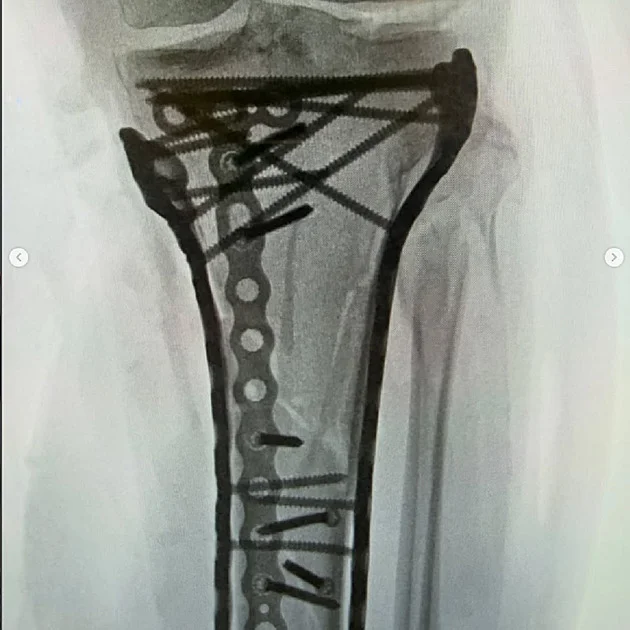

Zdroj foto: www.echo24.cz „Budu v pořádku.“ Vonnová má za sebou třetí operaci, sdílela foto poraněné nohy Americká lyžařská legenda Lindsey Vonnová po drastickém pádu v olympijském sjezdu, při kterém si zlomila nohu, podstoupila v Itáli... Zdraví -17 dny Echo24.cz

Zdroj foto: www.lidovky.cz Už pátá operace, šest hodin dlouhá. Bolest zvládám těžko, přiznává Vonnová Americká lyžařka Lindsey Vonnová má za sebou pátou operaci nohy, kterou si zlomila při pádu v olympijském sjezdu. Zákrok trval pře... Zdraví -9 dny Lidovky.cz